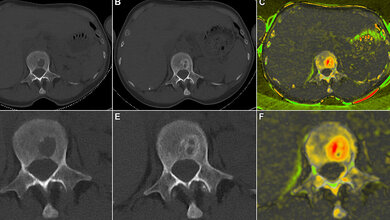

Jede Krebserkrankung ist anders, so auch beim Multiplen Myelom. Tumorherde entwickeln sich individuell verschieden und mit unterschiedlicher Geschwindigkeit. Das erschwert eine Einschätzung des Krankheitsverlaufs und die Wahl der optimalen Behandlung. Während sich veränderte Plasmazellen manchmal nur wenig verbreiten, verhalten sie sich in anderen Fällen äußerst aggressiv, was mit einer schlechten Perspektive für den weiteren Krankheitsverlauf einhergeht. Was also macht die Verläufe bei Multiplem Myelom so unterschiedlich? Gemeinsam mit Experten für Proteinanalysen des Max Delbrück Center und des BIH haben die Forschenden genetische und molekulare Veränderungen in den Tumorzellen bei einer Gruppe von mehr als einhundert Erkrankten im Detail untersucht. Eingeflossen sind Daten von Patienten der Deutschen Studiengruppe Multiples Myelom (DSMM), die am Universitätsklinikum Würzburg koordiniert wird. Die Forschenden konnten somit auch klinische Daten von einheitlich behandelten Patienten über einen Zeitraum von acht Jahren und länger nach der Erstdiagnose einbeziehen.

Neueste massenspektrometrische Methoden ermöglichten es, das Proteinprofil entarteter Plasmazellen zu erstellen und mit dem Profil gesunder Plasmazellen von nicht erkrankten Personen zu vergleichen. Das Ergebnis: Sowohl genetische Veränderungen als auch Veränderungen in den Signalwegen führen zu einer unkontrollierten Aktivierung der Krebszellen. Regulatorische Prozesse auf der Proteinebene hatten dabei den stärkeren Einfluss. Die Forschenden konnten eine Proteinkonstellation ausfindig machen, die unabhängig von bekannten Risikofaktoren auf einen besonders aggressiven Krankheitsverlauf hinweist.